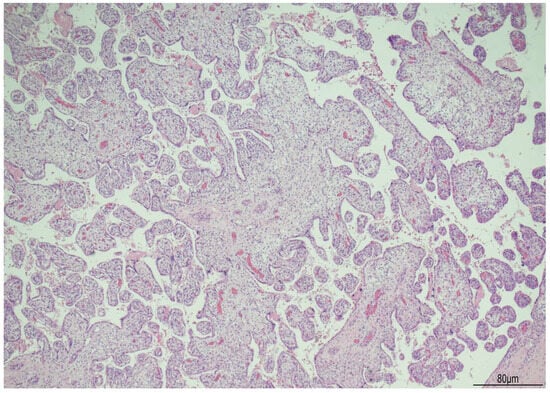

Histologically, OMN was the most striking finding in both kidneys. The cortex was thinned, with the glomeruli overall reduced, most of them hypoplastic, but a few hypertrophic. The proximal tubules were enlarged as well. In the medulla the tubules were scattered and intermixed with the mesenchymal stroma (Figure 7).

Figure 7.

Oligomeganephronia (OMN). Both kidneys presented cortical thinning, and in the medulla, the mesenchymal stroma appeared increased, with a relative reduction in tubules. Glomeruli were overall reduced and hypotrophic (black arrows), as a compensation focal glomerular hypertrophy was present (blue arrows); proximal tubules were also dilated (Hematoxylin and Eosin 10HPF).

At the postmortem, the facial features were consistent with WHS: broad forehead, hypertelorism, flat nasal bridge, deep philtrum, downturned corners of the mouth, microretrognathia, and low-set and posteriorly rotated ears. A mild growth restriction was also evident with a weight of 456 g (normal for gestational age: 510 +/−97 g) and a crown–heel length of 30.1 cm (normal for gestational age: 29.1 +/−2 cm) (13). Externally, ventral hypospadias with a posteriorly located urethral meatus was observed. The internal examination showed severely hypoplastic kidneys, measuring 12 mm in longitudinal diameter and weighing 0.1 g each. Histologically, the most striking feature was bilateral OMN. The cortex appeared thinned, with an overall reduction in glomeruli, most of which were hypoplastic, though a few were hypertrophic. The proximal tubules were also enlarged. In the medulla, the tubules were dispersed and interspersed with the mesenchymal stroma.

Histologically, microdissection studies have shown, in the early stages of the disease, enlargement of the whole nephron, involving the glomeruli, juxtaglomerular apparatus, and tubules. The capillary loops are also increased in number. Due to hypertrophy of the glomeruli and tubules, glomerular density is reduced, with fewer glomeruli per millimeter of cortex compared to age-matched controls. The disease evolution includes segmental and total glomerulosclerosis with tubulointerstitial scarring [17].